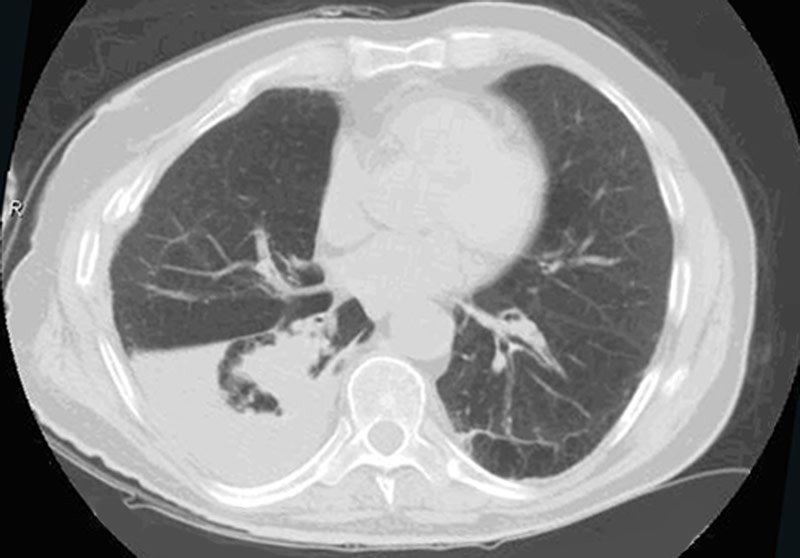

Although surgical management of patients with severe flail chest is at present controversial, we think that surgical stabilization is strongly indicated in specific clinical situations. The effectiveness and the ideal timing of chest wall stabilization in patients on mechanical ventilation is related to the degree of the pulmonary parenchymal damage [7,8]. The presence of extensive pulmonary contusion (Figure 1) is a relative contraindication to surgical stabilization. These patients require prolonged ventilation, and an early surgical stabilization would not provide benefit [7,8]. However, a surgical procedure can be proposed if the patient fails to wean from the ventilator once a partial resolution of pulmonary contusion is achieved [9,10].